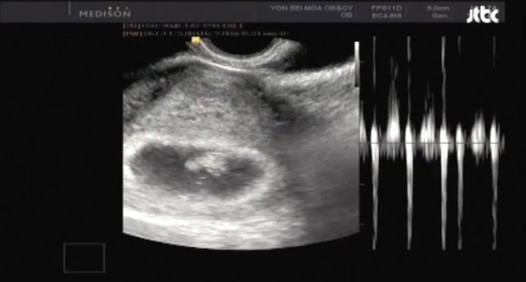

#초음파 검사- 태아 목덜미 투명대 측정

임신 10~14주에 실시하는 검사다. 초음파를 이용해 태아의 목 뒤 피하 두께를 측정하는 검사로 태아의 염색체 이상 위험도를 알 수 있다.

검사 결과 피하 두께가 증가돼 있는 상태는 염색체 이상이 있을 가능성이 높으므로 혈액검사를 추가로 하거나 융모막 융모 검사, 양수 검사를 해야 한다. 특히 이 검사와 함께 혈액검사를 병행하면 태아의 염색채 이상을 더 정확하게 찾을 수 있다.

사진출처: JTBC '우리가 사랑할 수 있을까' 캡처 / 자료출처: 국가건강정보포털